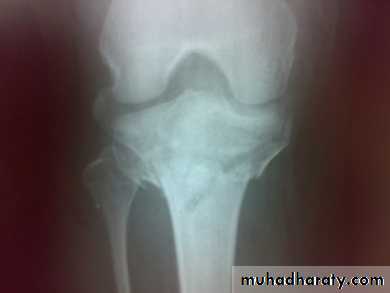

Imaging : X-ray

: anteroposterior, lateral & oblique views.

CT -Scan may used to detect amount of depression and comminuation.

Tibial plateau fracture